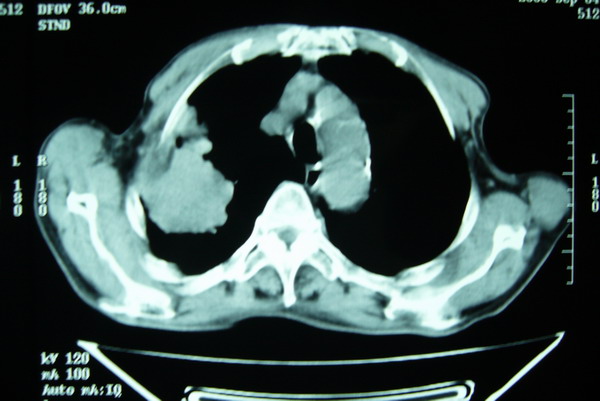

右肺上叶巨大软组织肿块,轮廓不规则,纵隔内有肿大淋巴结,首先考虑肺癌。

右上肺一不规则团块,边缘有分叶和毛刺,纵隔有淋巴结肿大。右肺周围性肺癌首先考虑。